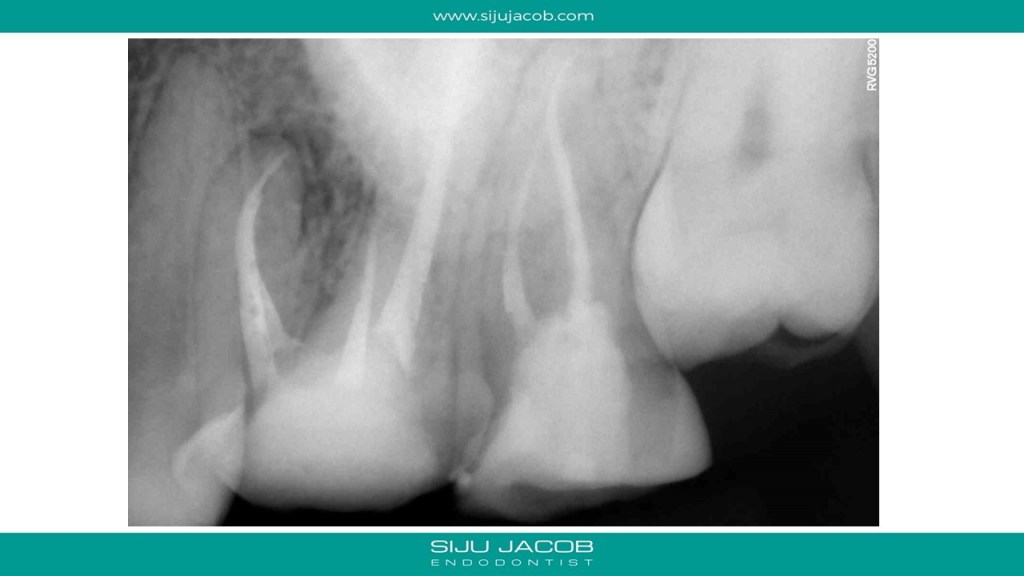

Some cases are such that when you eventually finish, you wonder what the fuss was all about. I struggled to locate the canals in this case. Not sure why. Yes, the access was difficult, but the main reason I struggled was probably the prior access that was made. This made me lose orientation initially. I managed to locate one canal and then took an Inter-appointment CBCT. This made things much easier. More in the short video below:

And below are the clinical slides of the same case: